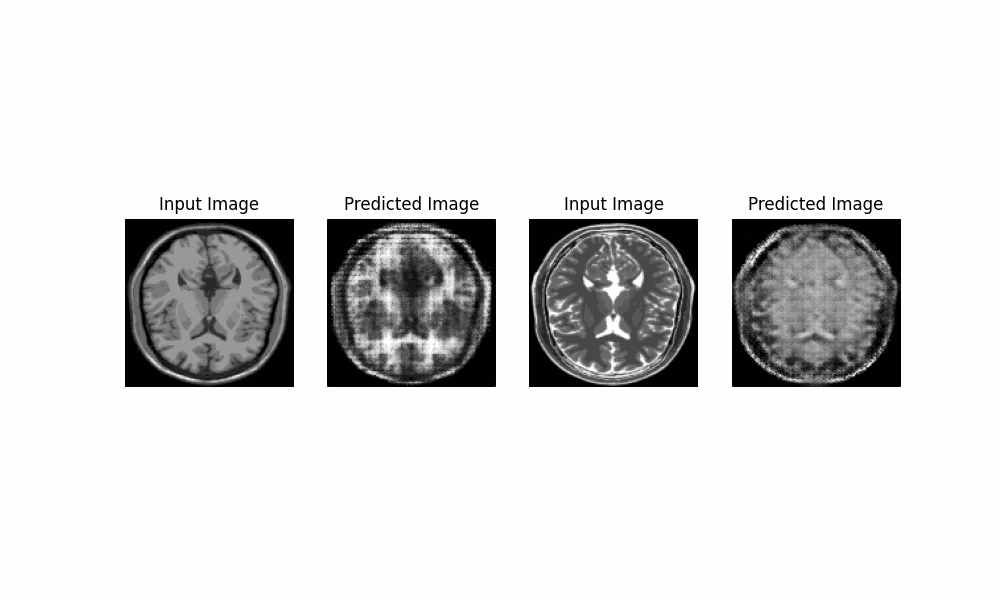

Artificial Intelligence & Computer Vision